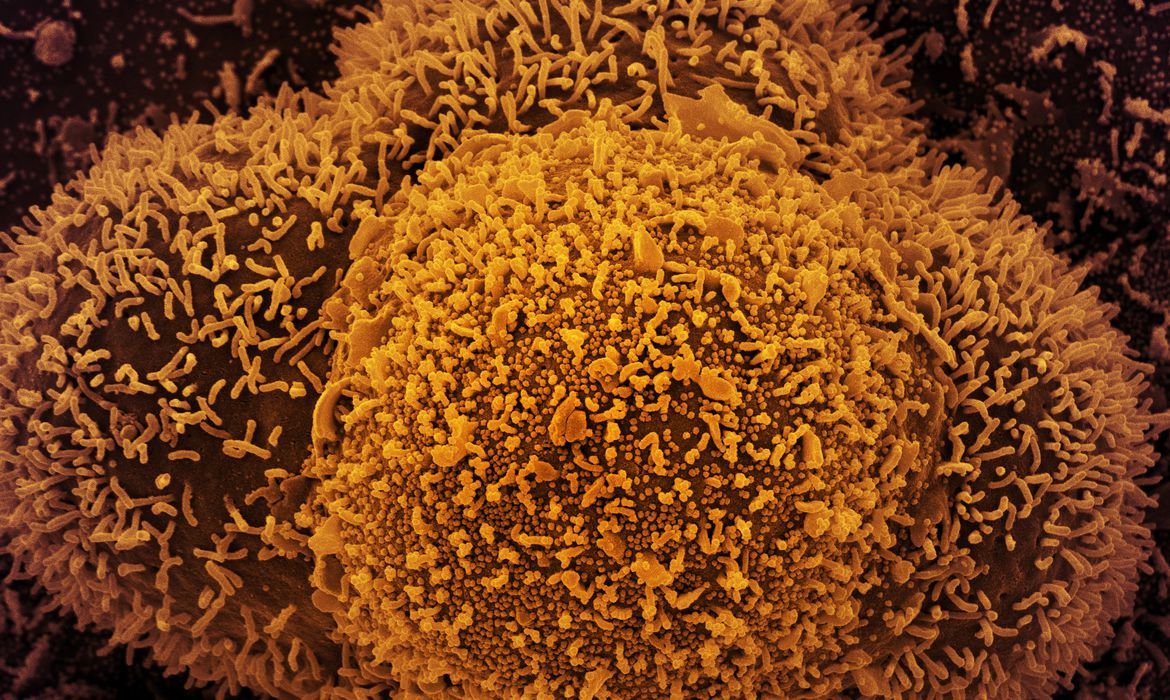

Foto: NIAID